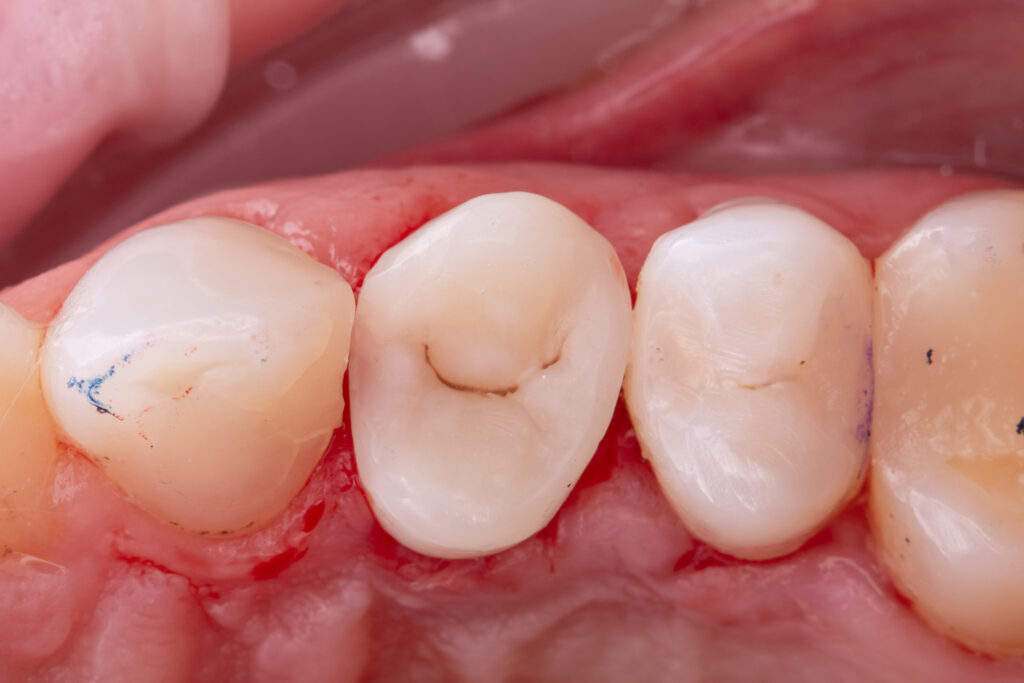

The second visit was dedicated to replacement of the old restoration and placement of a fiberglass post (EverX Dentin Shade was used), followed by restoration with Asteria A1B+, NeoSpectrum A2, and Enamel Brown stain.

The total time for restoration replacement was 1 hour and 30 minutes.